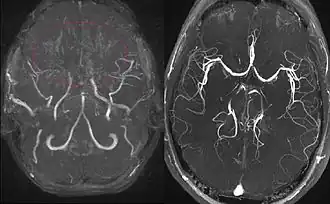

Right: healthy patient, for comparison.

Cerebral angiography is the gold standard of diagnosing moyamoya disease and its progression. According to Suzuki's system, it can be classified into six stages:[12]

Magnetic resonance angiography (MRA) is also useful in diagnosing the disease with good correlation with Suzuki's grading system.[12]